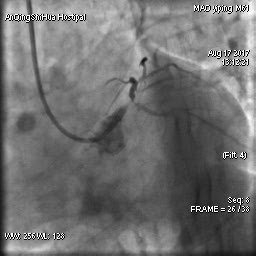

然而,冠狀動(dòng)脈造影的結(jié)果讓所有人都大吃一驚!

毛先生的血管在心臟左主干體部及分叉部都出現(xiàn)嚴(yán)重狹窄,僅一絲血流通過,前降支的血流已明顯減慢。難怪日常步行都會(huì)引起心絞痛,毛先生隨時(shí)都可能心臟驟停。

術(shù)前 心臟左主干末端嚴(yán)重狹窄